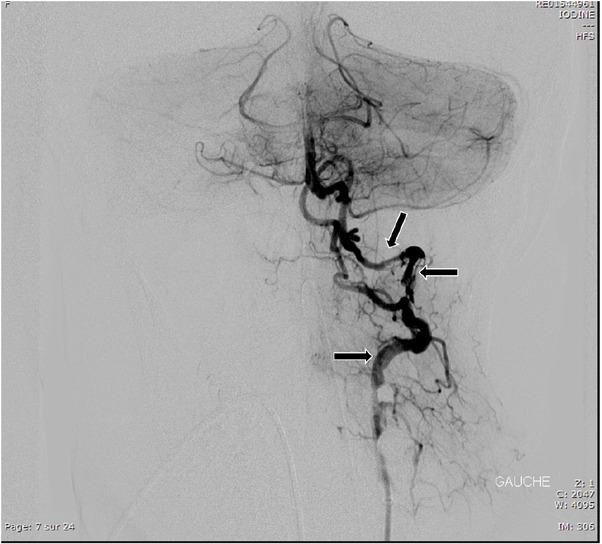

Fig. 4